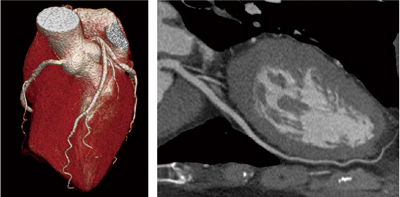

ViSION Editionにおける最も大きな進化は,320列検出器を搭載したAquilion ONEの特長を維持したまま,1回転0.275秒の高速撮影を実現した点にある。これにより,心臓撮影における1心拍の低被ばくスキャンを,従来よりも高心拍な患者群に適用できるメリットが期待される(図5)。また,体動を抑制することが難しい小児撮影や,Area Detector CTの特長である動態撮影における1画像あたりの時間分解能向上など,動きのある患者さんに対する撮影精度向上が期待される。

図5 71bpmの心臓1心拍撮影 臨床画像例(ViSION Edition 0.275秒回転にて)

(データご提供:藤田保健衛生大学病院様)